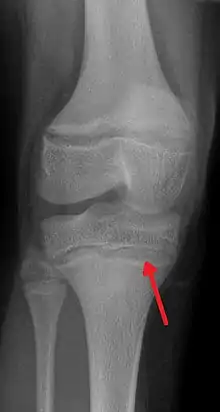

En cas de saturnisme chronique et important, apparait sur les radiographie osseuses d'os longs une ligne blanche parfois dite métaphyséale. Elle se forme aux environs de la zone de production du cartilage[1]. ce phénomène a notamment été décrit en 1933 par Vogt[2] puis par Park & al. [3]